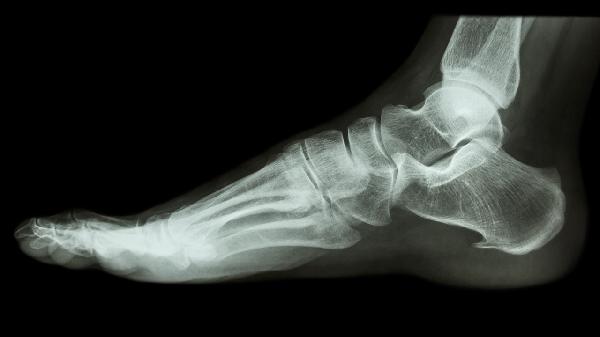

骨囊肿虽然是一种良性病变,但如果不及早治疗,可能导致严重的并发症,如病理性骨折和骨骼畸形。对于怀疑患有骨囊肿的患者,应及时就医,进行详细的影像学检查和病理诊断,以便制定合适的治疗方案。通过合理的治疗和监测,大多数患者可以获得良好的预后,恢复正常的骨骼功能。